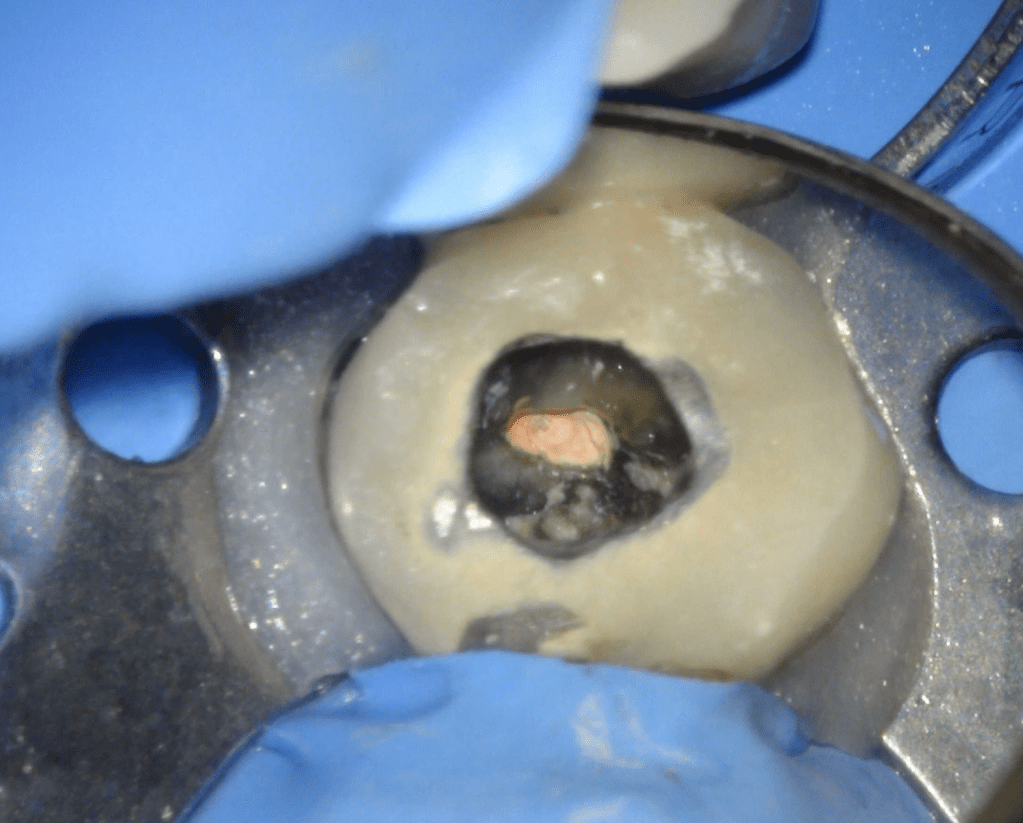

Reco pared vesticular